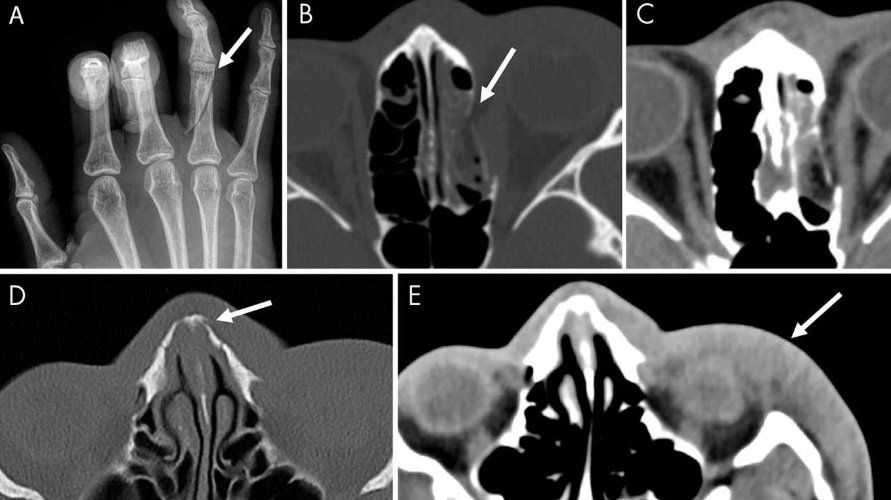

El investigador principal del estudio, Bharti Khurana, radiólogo del Hospital Brigham And Women y profesor en la Escuela de Medicina de la Universidad de Harvard explicó: “La radiología hizo contribuciones sustanciales a la detección de traumas no accidentales en chicos, y la identificación de la violencia pediátrica es un componente esencial de la capacitación de un radiólogo, pero se sabe poco sobre el papel de las imágenes en la detección de violencia de género“. “Las imágenes médicas pueden ofrecer pistas tempranas según la ubicación y el patrón de las lesiones nuevas y antiguas“, amplió.

– Las fracturas agudas y los hallazgos obstétricos/ginecológicos, como pérdida del embarazo y restricción del crecimiento intrauterino, se asociaron con de 2 a 4 veces más probabilidades de violencia.

El objetivo final de la investigación, según Khurana, es “desarrollar un sistema integrado que use patrones derivados del análisis experto de imágenes clínicas y datos clínicos, detecte y clasifique las lesiones, y avise a los médicos clínicos si las lesiones de un paciente tienen un nivel bajo o probabilidad de alto riesgo de ser el resultado de la violencia de género”. En la siguiente fase del estudio, los investigadores planean usar el aprendizaje automático para reconocer los signos de la violencia y crear un sistema de alerta para una mayor confianza y solidez en los resultados, permitiendo a los proveedores de atención médica iniciar un diálogo con sus pacientes.